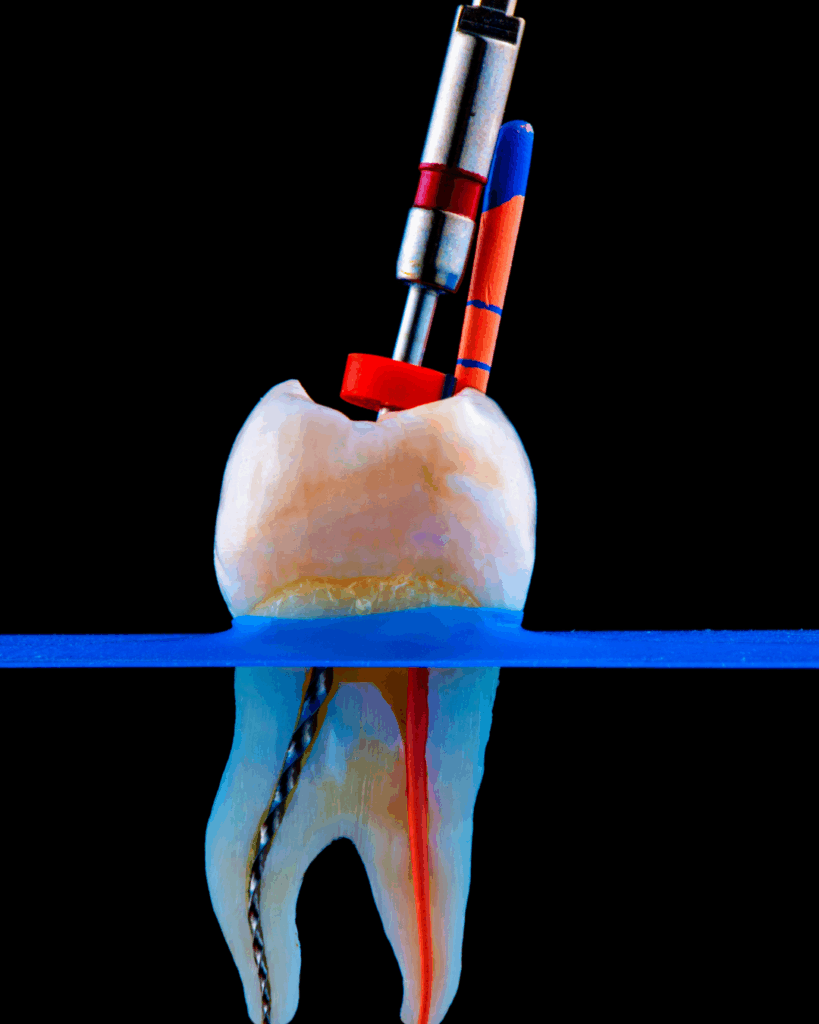

Como Funciona o Tratamento de Canal?

Passo a Passo do Procedimento

- Avaliação e Diagnóstico- O dentista realiza exames clínicos e radiografias para confirmar a necessidade do tratamento de canal e determinar a extensão do dano.

- Anestesia Local- A área é anestesiada para garantir o conforto do paciente durante o procedimento.

- Abertura do Dente- O dentista faz uma abertura na parte superior do dente para acessar a polpa danificada.

- Remoção da Polpa- A polpa infectada ou morta é removida, e o canal é completamente limpo e desinfetado.

- Preenchimento do Canal- Após a limpeza, o canal é preenchido com um material específico (geralmente a guta-percha) para evitar novas infecções.

- Restauração do Dente- Por fim, o dente é selado com uma restauração provisória ou permanente, e, em alguns casos, pode ser necessário colocar uma coroa para reforçar a estrutura do dente.